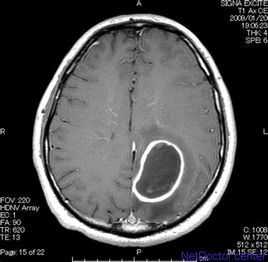

腦膿腫

指由化膿性細(xì)菌引起的腦組織的化膿性感染。病原可分為耳源性、鼻源性、血源性、隱源性或損傷性。主要表現(xiàn)為隱性感染、顱內(nèi)壓增高及腦局灶性癥狀和體征。